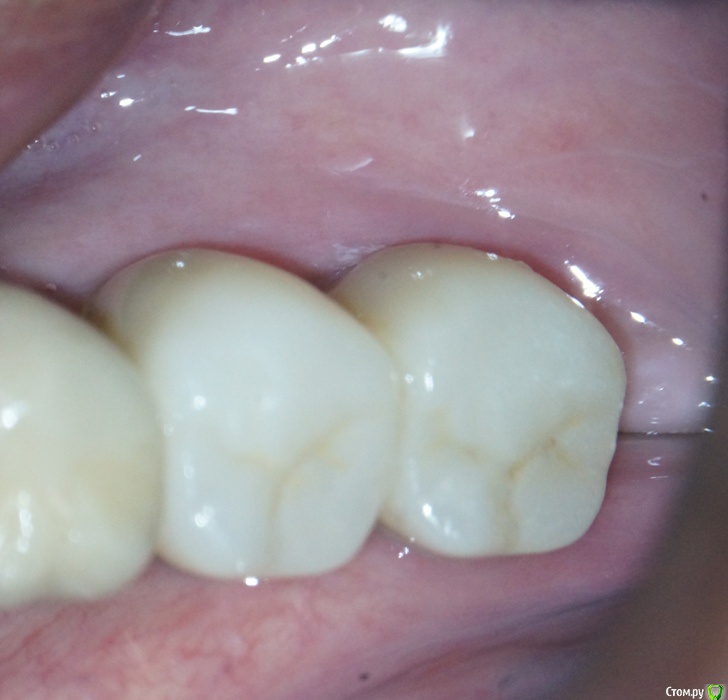

annda Опубликовано 3 августа, 2020 Поделиться Опубликовано 3 августа, 2020 (изменено) Стоял до этих имплантатов суперлайн коротыш 7мм,одиночка.Заколебались с раскруткой винта,ходила каждый месяц.Плюнула,решили выкрутить,переставить на эти.КТ после удаления. Изменено 3 августа, 2020 пользователем annda 1 Ссылка на комментарий

annda Опубликовано 4 августа, 2020 Поделиться Опубликовано 4 августа, 2020 Что-то с загрузкой пошло не так,извините.Контроль после постановки и контроль с абатментами(через 3 месяца) Ссылка на комментарий